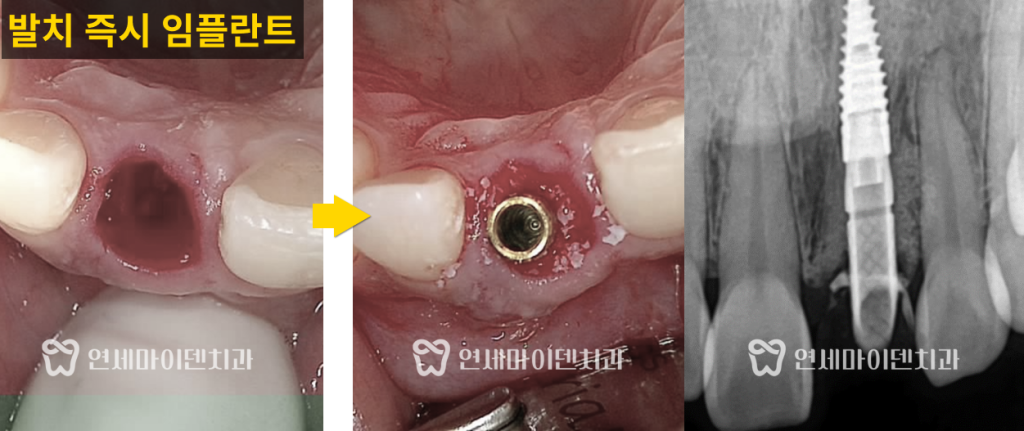

문제의 앞니를 발치한 뒤 발치된 치아 상태를 살펴보면

뿌리 한가운데 구멍이 뚫려있는 것이 확인됩니다.

뿌리 끝쪽부터 손상이 됐다면 손상된 부분만 절제하는

치근단 절제술을 시도할 수 있지만,

이렇게 가운데 구멍이 뚫린 경우 손상된 부위만 치료하기 어렵기 때문에

발치를 해야하는 상황이 맞았다고 볼 수 있습니다.

발치 후 내부에 퍼져있는 염증을 깨끗하게 제거했습니다.

이후 모의수술로 계획한 정환한 위치에

임플란트를 식립하였습니다.

추후 심미적으로 자연스러운 잇몸을 만들기 위해

임플란트를 정중앙이 아닌 입천장 쪽으로 살짝 틀어서 식립하였습니다.

특히, 치근 내흡수로 뼈가 많이 녹았기 때문에

임플란트 식립과 동시에 뼈 이식도 충분히 해준 뒤 치료를 마무리했습니다.